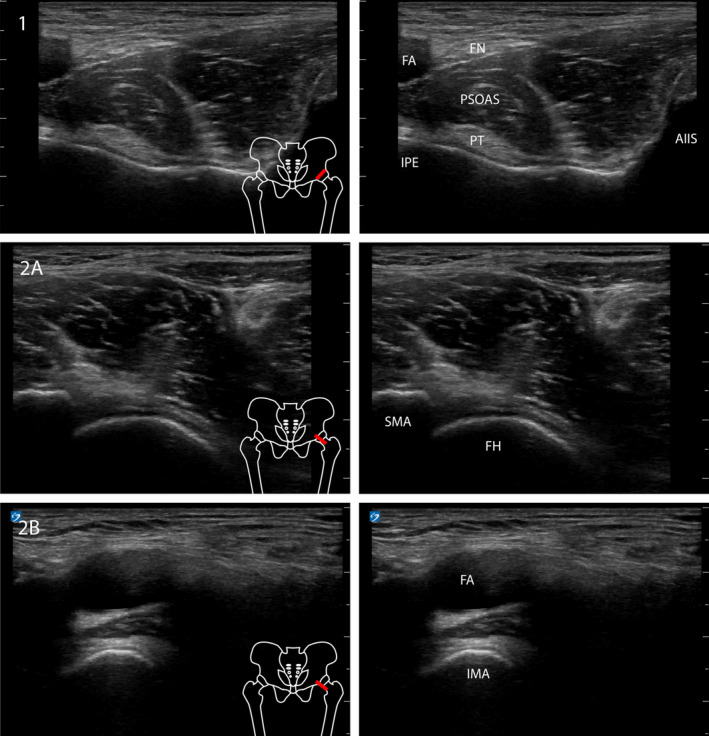

Objectives: In this study, the spread of methylene blue was compared between an ultrasound-guided Pericapsular Nerve Group (PENG) block and a double injection technique, where the approach towards the inferomedial acetabulum was added to the latter.

Methods: The two techniques were performed in 11 fresh frozen cadavers. The spread was measured after anatomical dissection in which the supplying femoral and obturator nerves were identified.

Results and conclusion: Our study demonstrates adequate staining of the iliac bone with comparable distal and medial spread in both techniques, indicating that the PENG block with a single injection is adequate in blocking the hip capsule with 10 mL local anesthetics. Staining of the femoral nerve occurred in 2/6 specimens after the PENG block, and staining of the obturator nerve in 1 specimen in each group.